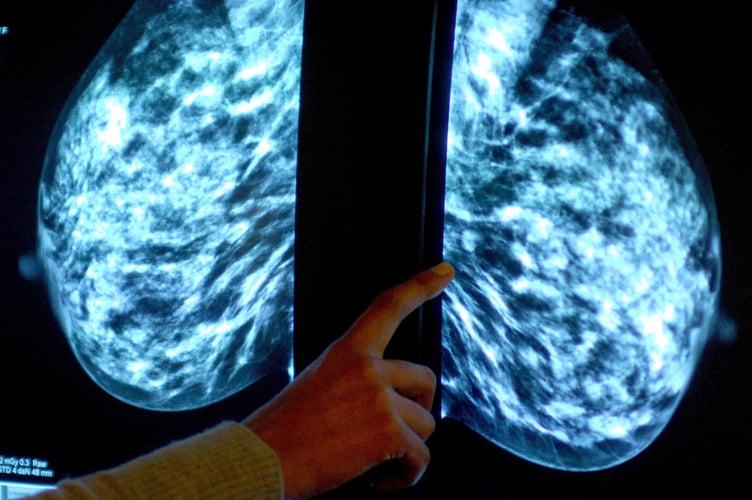

Dr Claire Knight, senior health information manager at Cancer Research UK, said: "Breast screening is an important tool for spotting the early signs of breast cancer at a stage when treatment is more likely to be successful.

"The current evidence suggests that breast screening reduces the number of deaths from breast cancer by about 1,300 a year in the UK."